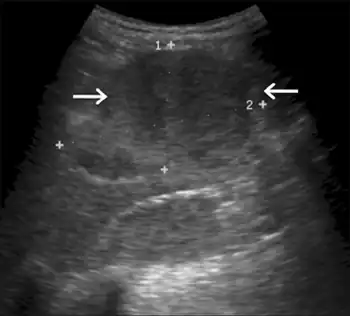

Hepatomegaly via CT scan.

Hepatomegaly with enlarged liver visible in red crosshairs and extending downward.

Impairment in the liver's ability to perform gluconeogenesis leads to clinically apparent hepatomegaly. Without this process, the body is unable to liberate glycogen from the liver and convert it into blood glucose, leading to an accumulation of stored glycogen in the liver. Hepatomegaly from the accumulation of stored glycogen in the liver is considered a form of non-alcoholic fatty liver disease. GSD I patients present with a degree of hepatomegaly throughout life, but severity often relates to the consumption of excess dietary carbohydrate. Reductions in the mass of the liver are possible, since most patients retain residual hepatic function that allows for the liberation of stored glycogen at a limited rate.

GSD I patients often present with hepatomegaly from the time of birth. In fetal development, maternal glucose transferred to the fetus prevents hypoglycemia, but the storage of glucose as glycogen in the liver leads to hepatomegaly. There is no evidence that this hepatomegaly presents any risk to proper fetal development.

Hepatomegaly in GSD type I generally occurs without sympathetic enlargement of the spleen. GSD Ib patients may present with splenomegaly, but this is connected to the use of filgrastim to treat neutropenia in this subtype, not comorbid hepatomegaly. Hepatomegaly will persist to some degree throughout life, often causing the abdomen to protrude, and in severe cases may be palpable at or below the navel. In GSD-related non-alcoholic fatty liver disease, hepatic function is usually spared, with liver enzymes and bilirubin remaining within the normal range. However, liver function may be affected by other hepatic complications in adulthood, including the development of hepatic adenomas.